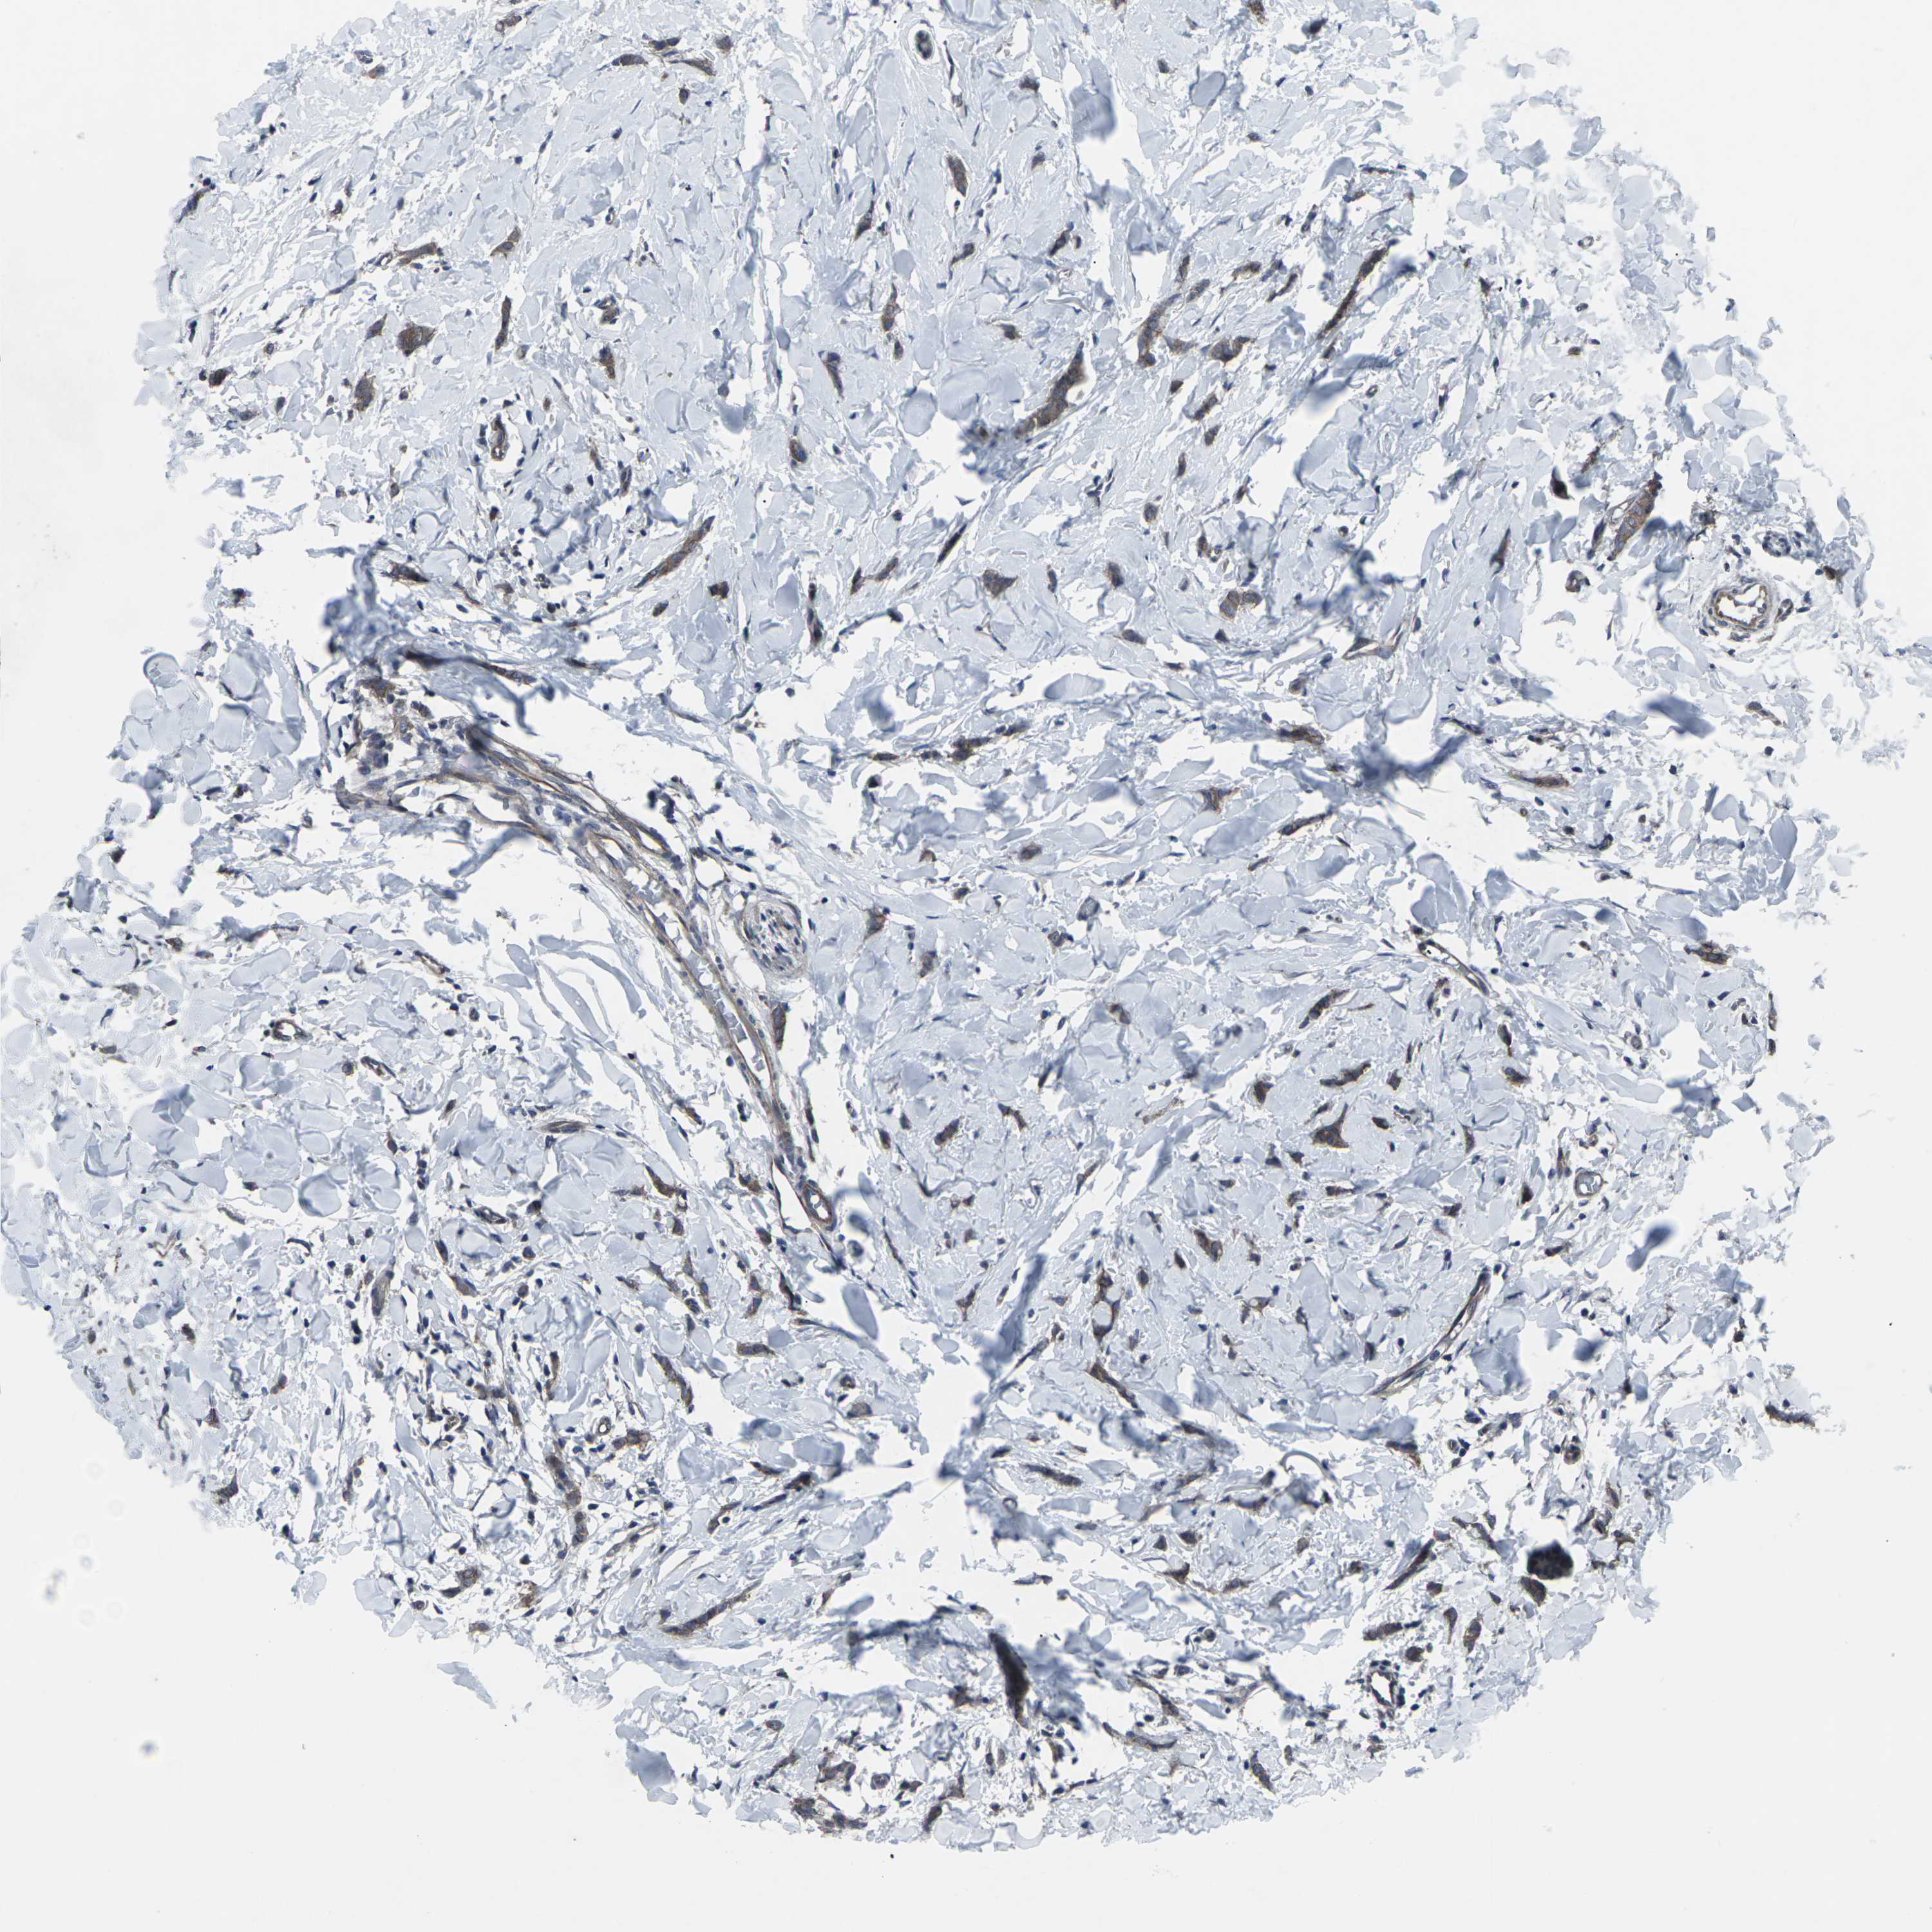

CANCER BREAST CANCER Show tissue menu

Breast cancer

Human cancer

MAPKAPK2 is not prognostic in Breast Invasive Carcinoma (TCGA)